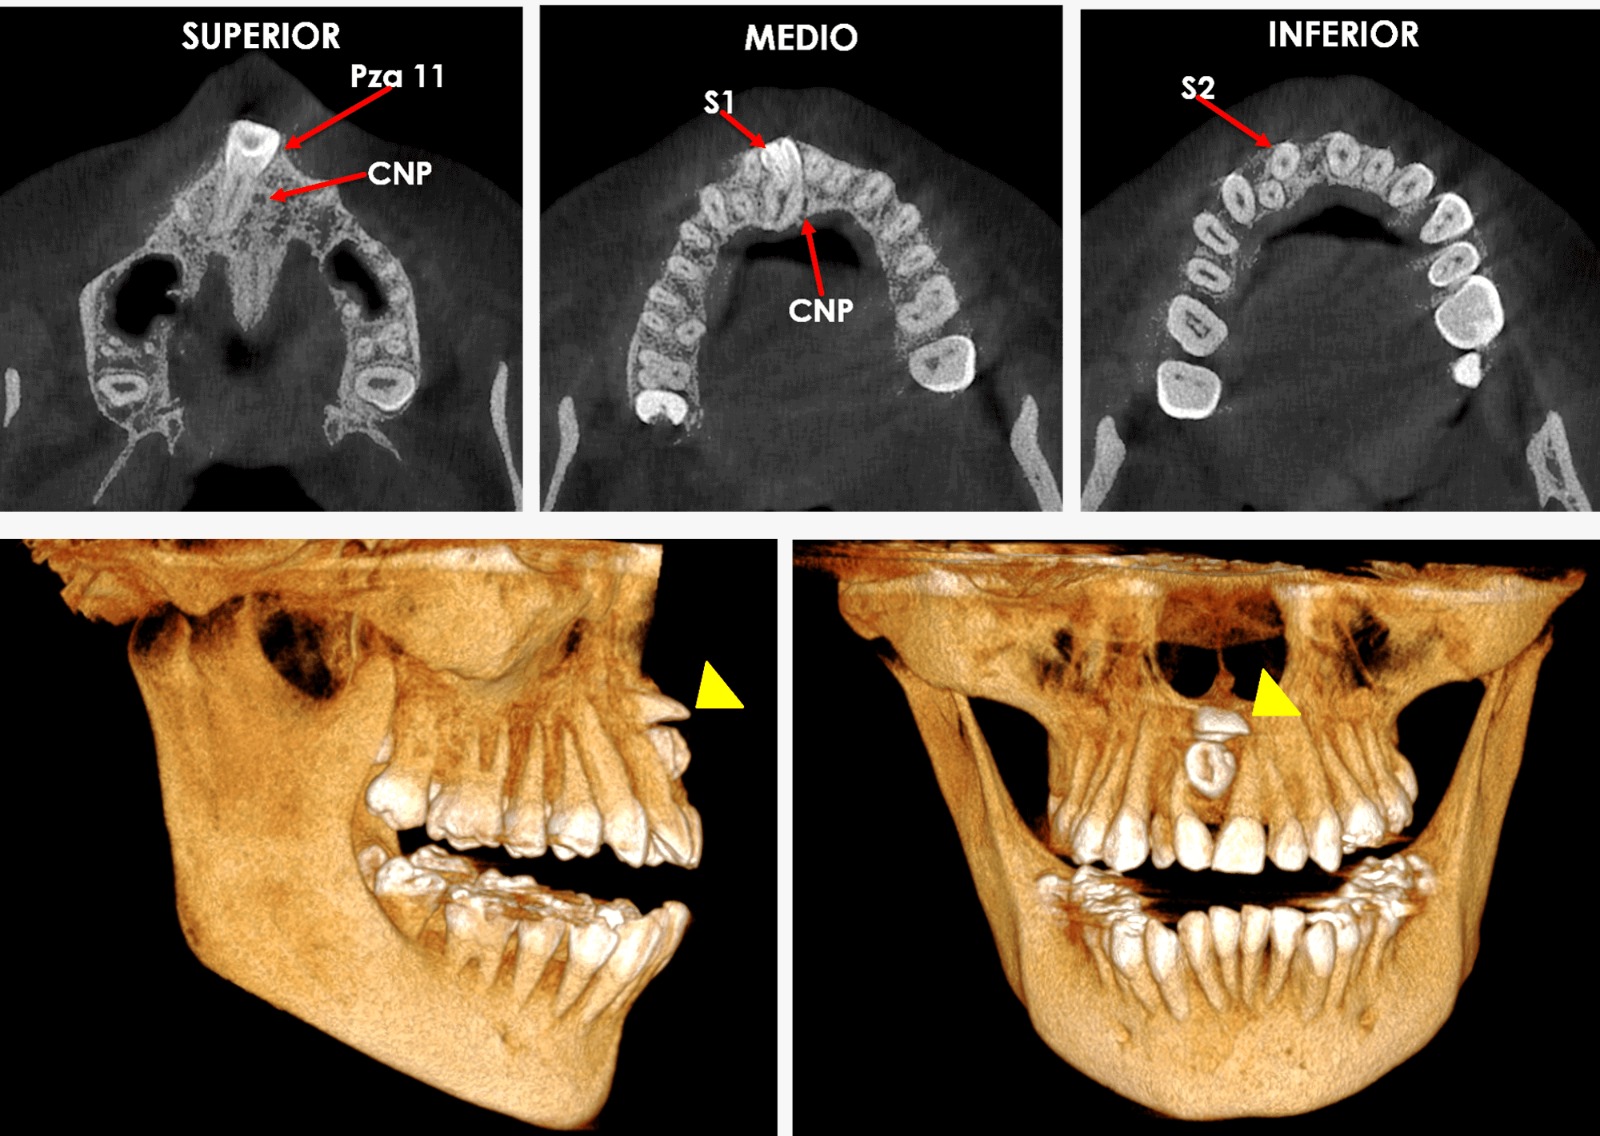

Tomografía dental

Diagnóstico

Precisión Digital

Eliminamos el margen de error mediante escaneo intraoral 3D y planeación digital milimétrica de cada tratamiento.